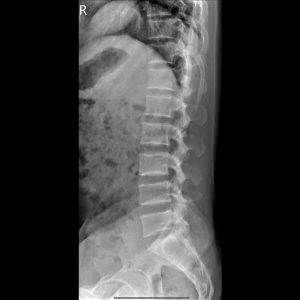

T-L spine AP view

T-L spine Lateral view